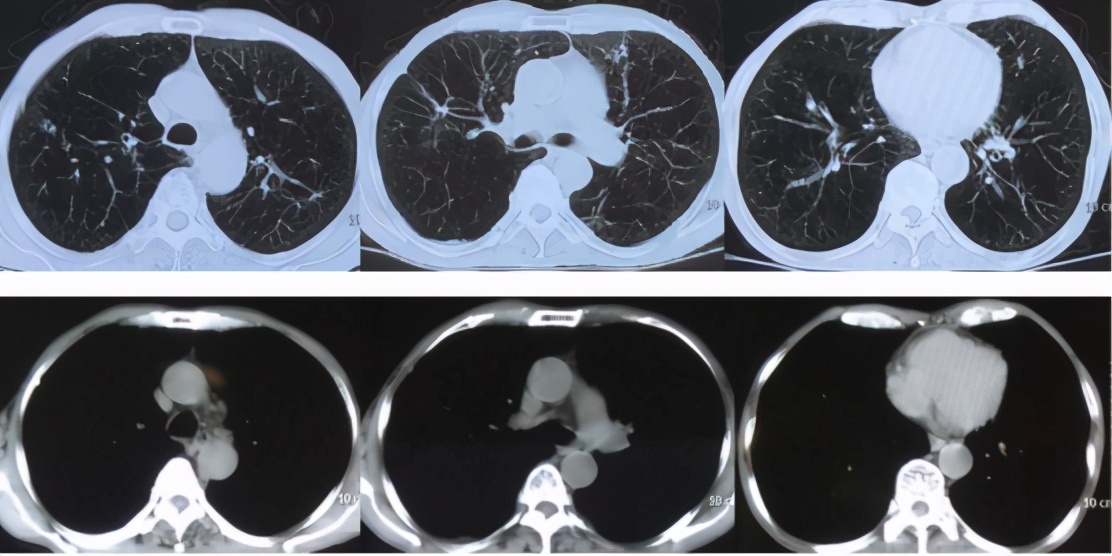

9、胸部CT:双肺多发纤维条索结节影,少许斑片渗出病灶;肺气肿;双侧胸膜增厚、粘连(图1)。

图1:肺部 CT(2017年07月11日)

值得一提的是,自7月11日患者入院后,右侧胸痛、气促的表现较前有所加重,并咳出金黄色水样痰,持续发热,呼吸衰竭迅速加重。我们对其行气管插管+有创呼吸机辅助通气。此时,患者的感染指标已迅速升高,血常规示:WBC 19×109/L,中性粒细胞百分比88.4%;PCT 5.27ng/ml;CRP 167mg/L;ESR 27mm/h;影像学也快速进展(图2)。

图2:肺部影像学(2017年7月11日~15日)